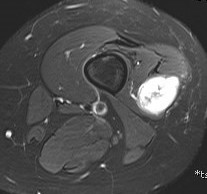

Show lesion on nerve periphery compared with neurofibroma which is in center of nerve

Schwannoma on tibialis posterior nervee

Schwannoma on tibialis posterior nerve